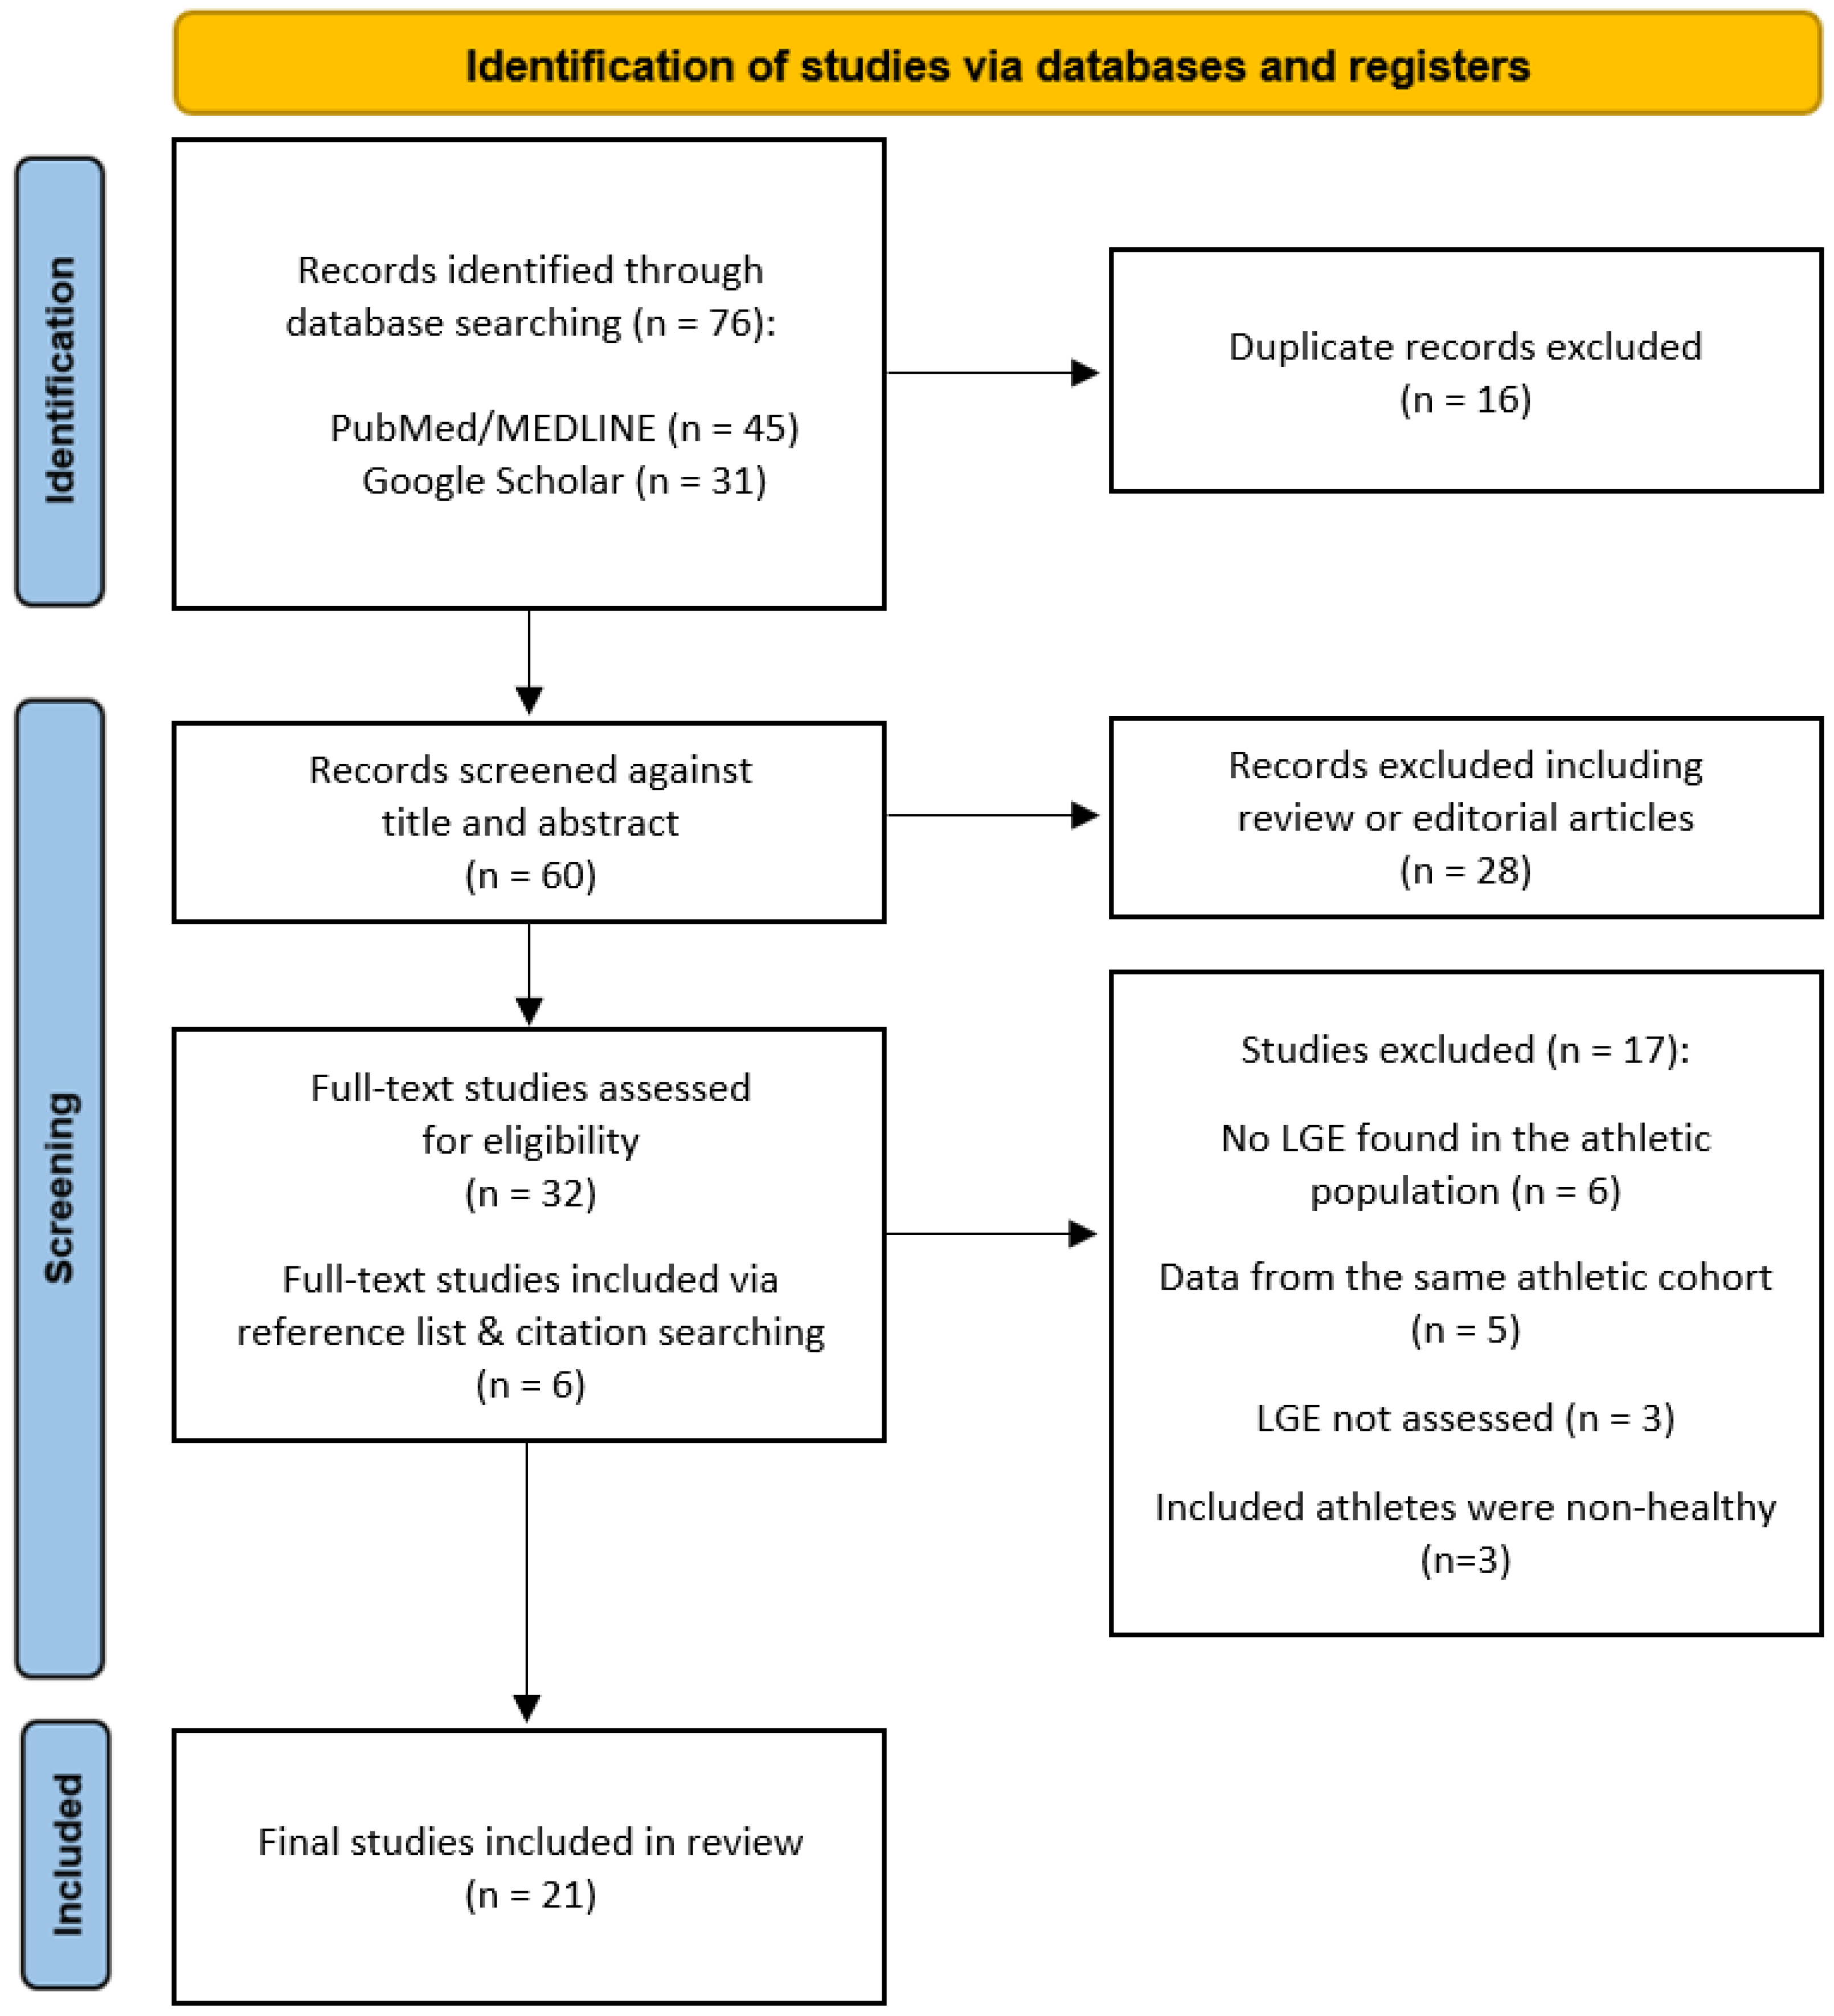

2. Methods

- Page, M.J.; McKenzie, J.E.; Bossuyt, P.M.; Boutron, I.; Hoffmann, T.C.; Mulrow, C.D.; Shamseer, L.; Tetzlaff, J.M.; Akl, E.A.; Brennan, S.E.; et al. The PRISMA 2020 statement: An updated guideline for reporting systematic reviews. BMJ 2021, 372, n71. [Google Scholar] [CrossRef] [PubMed]